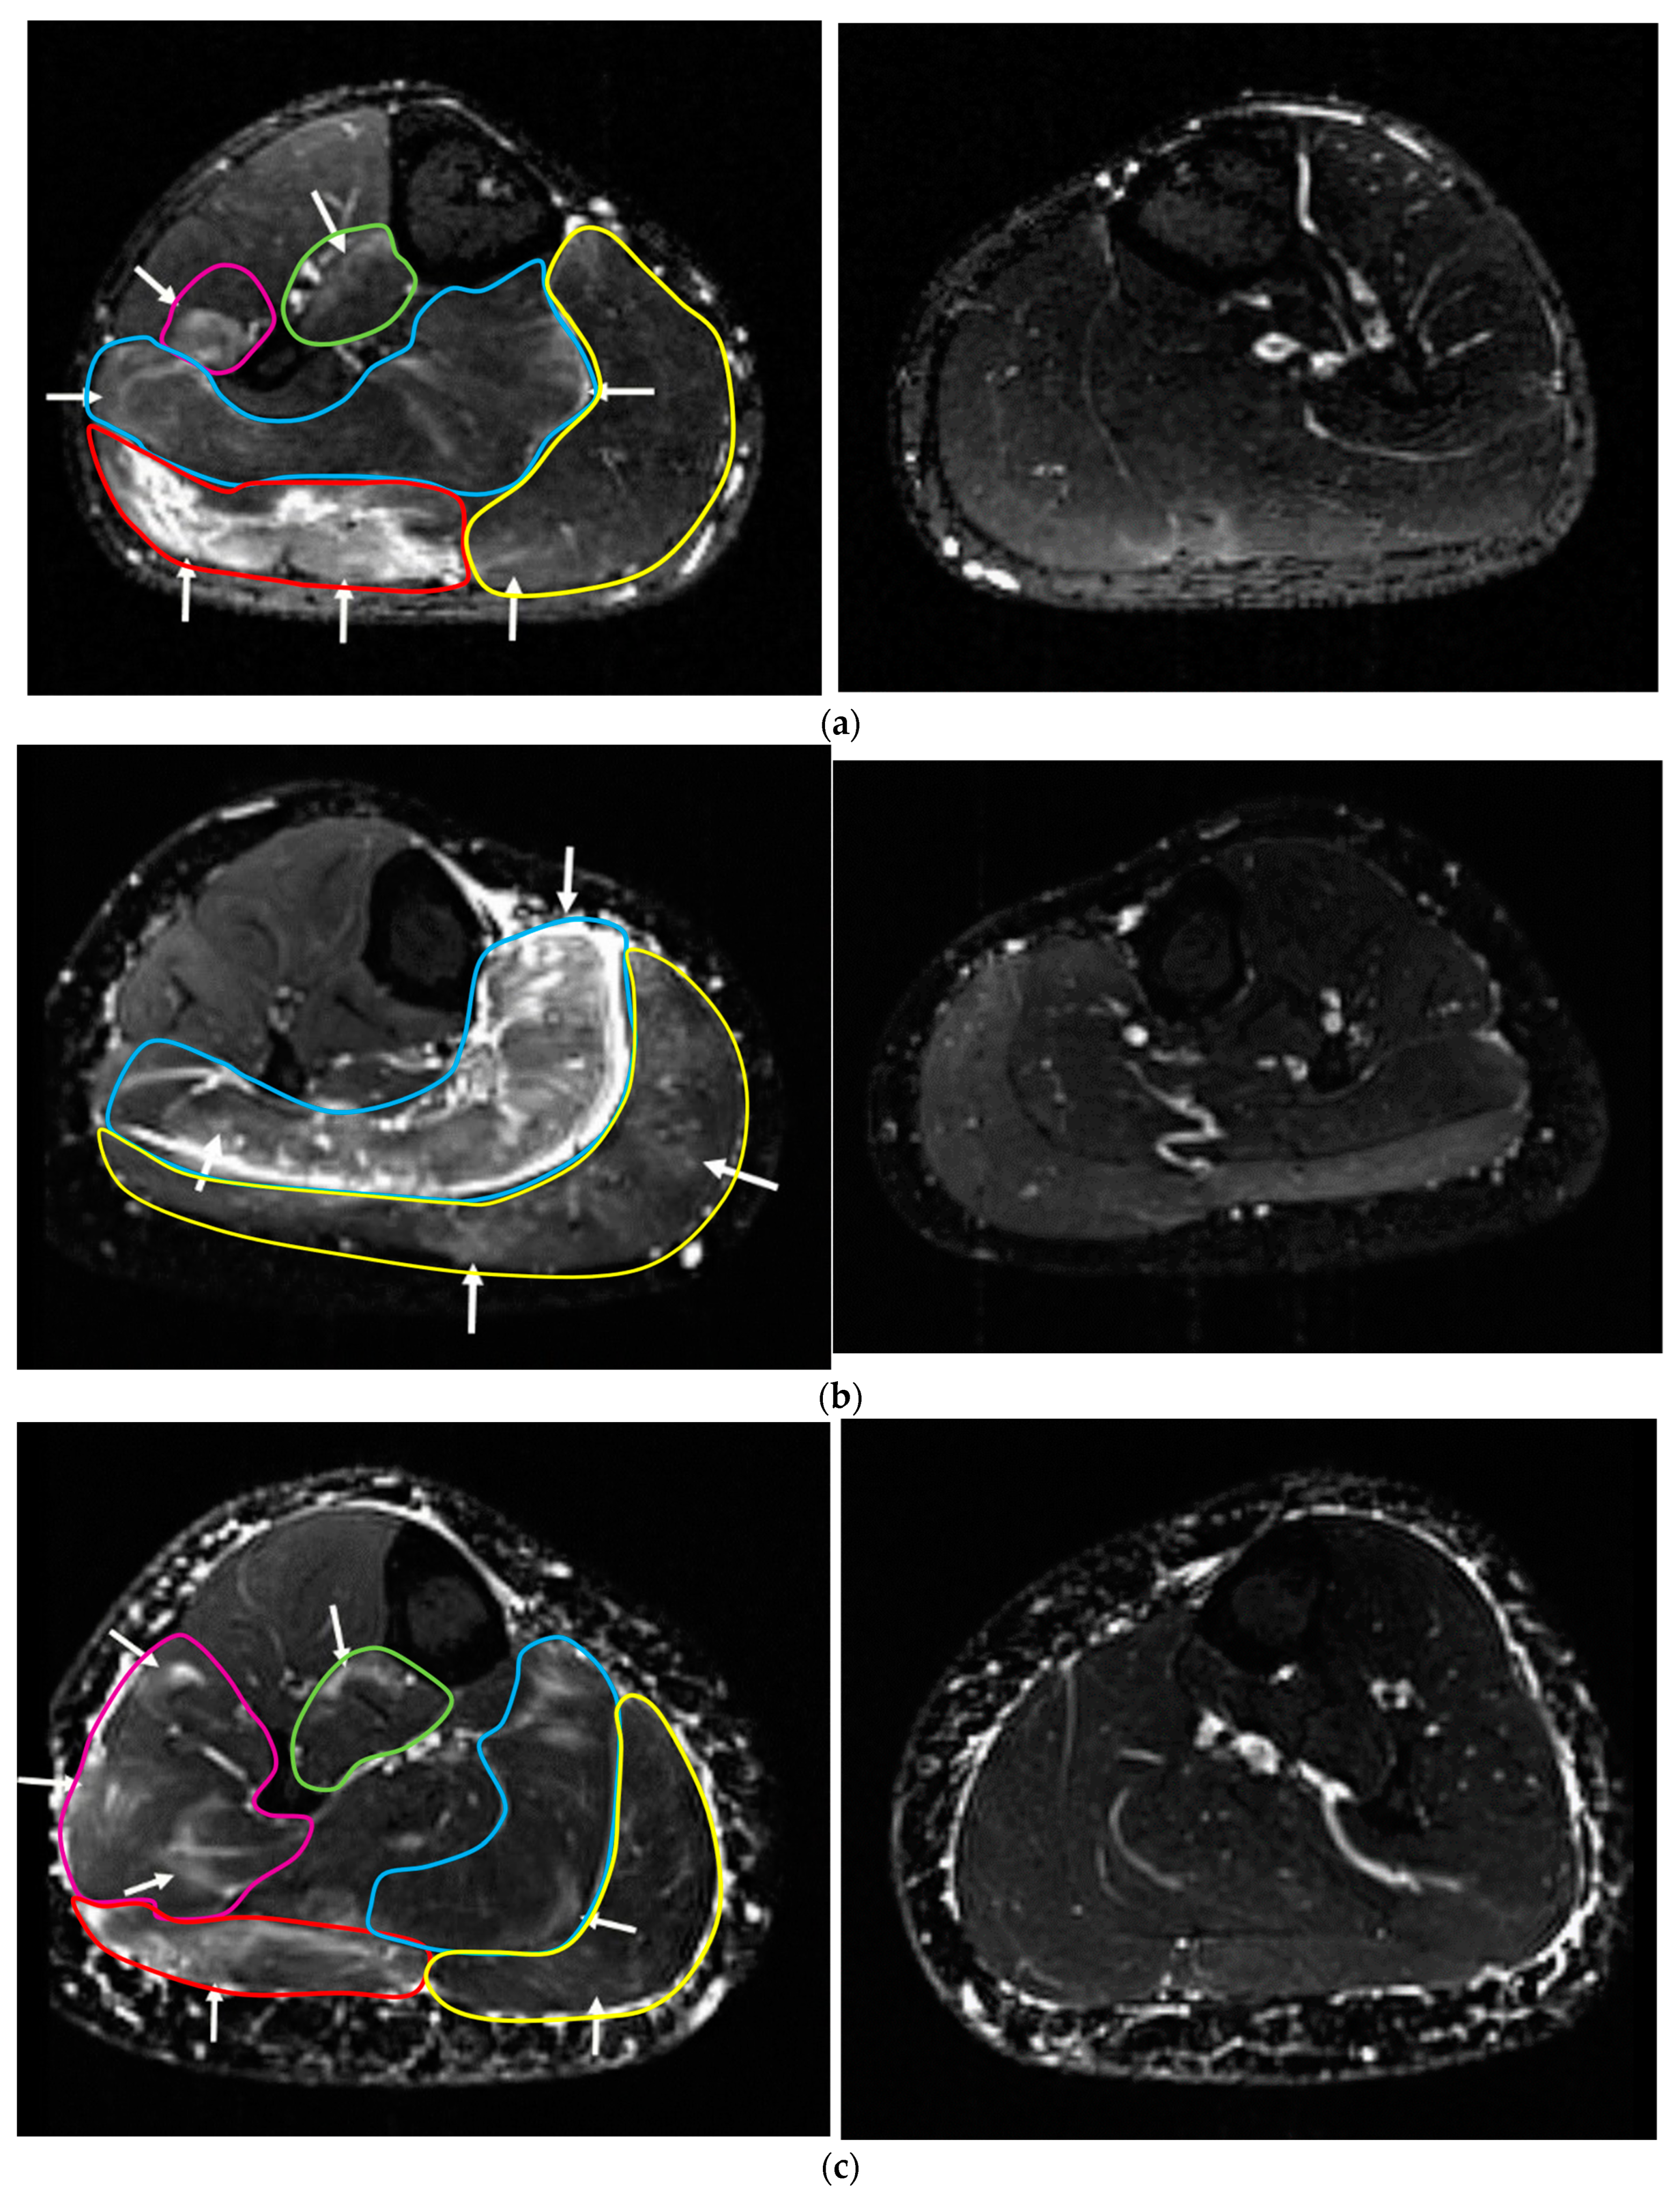

3.3.1. Upper Leg

3.3.2. Lower Leg

| Compartment of the Edema | Participants with Edema (Total: n = 8) | Maximum Depth of the Edema from Skin (mm) MV ± SD, (Range) | Intramuscular Edema Volume (Grading) MV (Range) |

|---|---|---|---|

| m. vastus lateralis | 4 | 29 ± 9; 19–39 | 1 (1) |

| m. vastus medialis | 2 | 25; 47 | 1 (1) |

| m. vastus intermedialis | 1 | 61 | 1 |

| m. rectus femoris | 0 | ------- | -------- |

| m. biceps femoris | 6 | 50 ± 12; 39–72 | 1 (1) |

| m. semimembranosus | 5 | 31 ± 6; 23–37 | 1 (1) |

| m. semitendinosus | 3 | 37 ± 6; 32–44 | 1 (1) |

| m. adductor magnus | 2 | 46; 68 | 1 (1) |